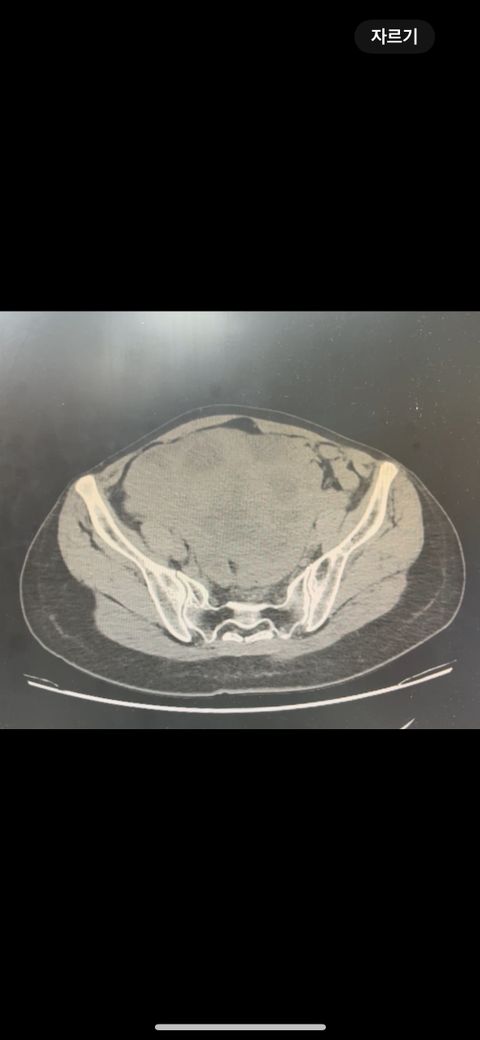

복부 ct 영상 판독부탁드립니다.!

결과는 3일 후 볼 예정인데 우선 영상만 받은 상태이고 너무 궁금한데 영상가지고 판독을 못해서요,,

이 사진가지고 확인할 수 있을까요 ?